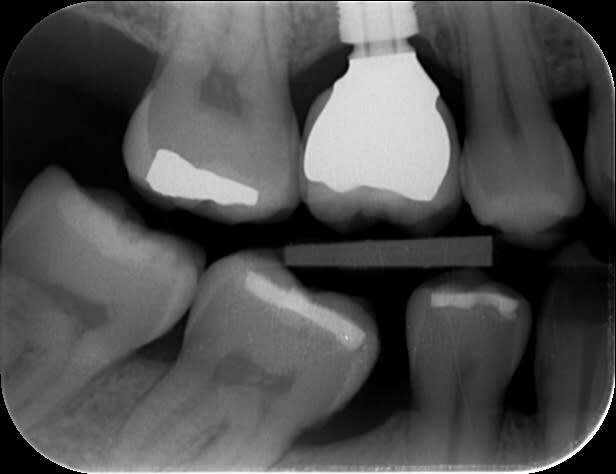

29/09/2017 à 13h50

tout chaud.

5x6 mm.

Contrôle régulier du fond du puits, et après le passage du dernier foret, je sens que c'est mou en distal.

le soufflement pas le nez ne produit pas de bulle, petit bout d'éponge hémostatique pour éviter que le filetage n'accroche, et pose.

il y plus qu'attendre...

Merci des avis exprimés.

6 mm uzbccs - Eugenol

cette forme trapue avec la connectique à 1mm du nonos je trouve que ça inspire confiance.